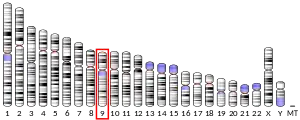

| External IDs | OMIM: 601978 MGI: 1195268 HomoloGene: 39965 GeneCards: SIGMAR1 | ||||||||||||||||||||||||||||||||||||||||||||||||||

Mutations in the SIGMAR1 gene have been associated with distal spinal muscular atrophy type 2.[34]